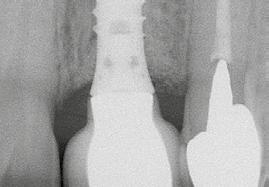

2. a–d ábra: PEEK zárócsavarok az implantátumokba helyezve, 1. eset (a). 2. eset (b). 3. eset (c), 4. eset (d). 3. a–b ábra: Röntgenfelvételek három hónap után (a) és a gyógyulási csavarok behelyezve (b, 1. eset). 4. a–b ábra: Röntgenfelvételek öt hónappal később (a) és a gyógyulási csavarok behelyezve (b, 2. eset). 2. táblázat: Az implantátum tulajdonságai.

lási csavarokat (PEEK titáncsavarral) maximum 15 Ncm-rel húztuk meg (3–6. ábra). Az összes implantátum kiváló stabilitást mutatott (a mérésekhez Periotestet használtunk, a Medizintechnik Gulden jóvoltából), és teljesen osszeointegrálódott. Ezt a radiológiai vizsgálatok is megerősítették.

tottuk (az okklúziós koncepciók alapján az implantációs pótlások nem voltak vezető fogak, és csak könnyű érintkezéseket alakítottunk ki, amelyeket artikulációs papírral ellenőriztünk). A páciensek instrukciókat kaptak a megfelelő szájhigiénére vonatkozóan, összpontosítva a fogköz kefékkel történő tisztítására. Végső kontroll röntgenfelvétel készült. A PEEK felépítmény nem radioopák, így az implantátum és a korona közötti távolság könnyen meghatározható a röntgenfelvételen: a felépítmény megfelelően illeszkedik az implantátumban, ha az implantátum válla és a korona alsó széle közötti rés 0,55 mm a röntgenfelvételen (8–11. ábra)

8. a–b. ábra: Végső röntgenfelvétel az implantátum helyzetéről (a) és a szájon belüli végső szituáció az 1. esetről (b).

Végső röntgenfelvétel az implantátum helyzetéről (a) és a szájon belüli végső szituáció a 2. esetről (b).

ábra: Végső röntgenfelvétel az implantátum helyzetéről (a) és a szájon belüli végső szituáció a 3. esetről (b és c).